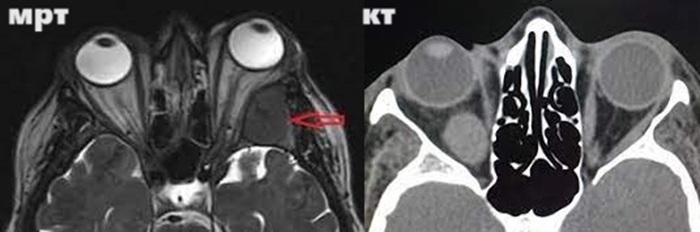

Оба исследования применяются достаточно редко. Офтальмология для выявления патологий чаще использует другие методы диагностирования. Но бывают сложные клинические ситуации, при которых требуется просканировать глазницу послойно. В этом случае медицинские специалисты решают, какое исследование глазных орбит провести: МРТ или КТ.

С помощью компьютерной томографии проще осмотреть костные структуры, вот почему ее используют, если есть предположение на переломы стенок орбиты.

Для выявления болезней глазных яблок и мышц, отвечающих за их движение, чаще назначают МРТ. Когда магнитно-резонансная диагностика обследуемому запрещена, то могут использовать КТ. При этом подбирают режимы сканирования, при которых мягкие ткани будут визуализироваться наилучшим образом.